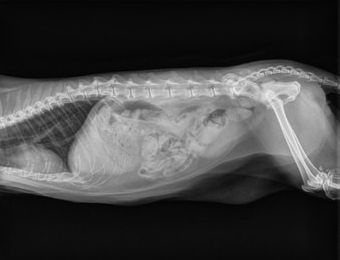

In-House Digital Radiography

South Paw Animal Hospital offers digital radiography at our hospital. Our Sound SmartDR digital imaging unit allows us to take clear and very detailed X-rays. For our patients, this is a much faster procedure as fewer images need to be taken. For our customers, we can share images digitally with them as well as referral specialty hospitals.

Radiographs can help evaluate health issues such as fractures, arthritis, cardiac abnormalities, or foreign body ingestion. Call (609) 465-9006 to schedule an appointment.